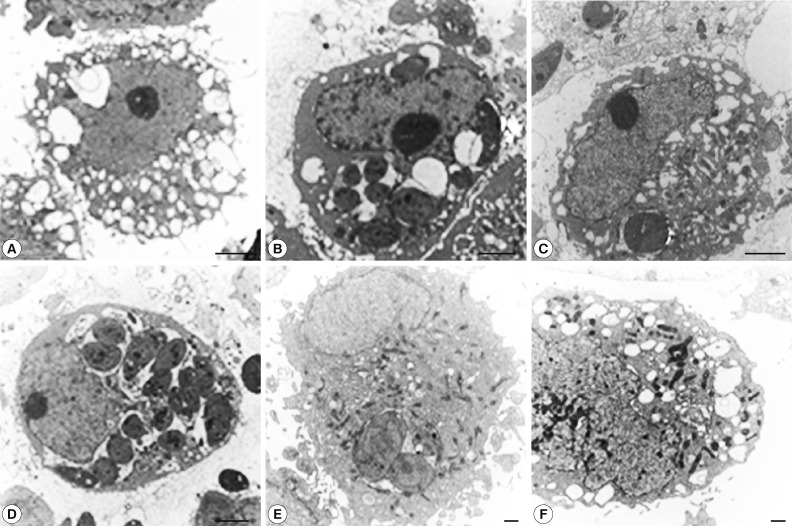

T. gondii proliferation in autophagic cells observed by TEM

To confirm autophagy, the cells infected with T. gondii and exposed to rapamycin were observed by TEM. Many autophagic vacuoles containing assorted organelles appeared in the cytoplasm of controls treated with rapamycin for 18 hr, and T. gondii proliferation in PVs was observed at 18 hr post-infection (Fig. 5A, B). Large numbers of autophagic vacuoles were visualized at 6 hr post-treatment in the T. gondii-infected, rapamycin-treated cells (Fig. 5C). However, the subsequent tachyzoite proliferation in PVs coincided with a decline in the numbers of AVs at 18 hr post-infection (Fig. 5D). Pre-treatment with the autophagy inhibitor, 3-MA for 2 hr significantly reduced the numbers of AVs, but the same effect was not seen after pre-treatment with wortmannin (Fig. 5E, F).

On TEM, numerous AVs were evident in the cytoplasm after 18 hr of rapamycin treatment as the control. It appears that, at 6 hr post-infection, the PVs containing tachyzoites and the AVs co-existed in the T. gondii-infected, rapamycin-treated cells. However, by 18 hr, the tachyzoites had begun to proliferate and the numbers of AVs had decreased (Fig. 5A, C, D).

Furthermore, we found that autophagic vacuolization was suppressed by pre-treatment with 3-MA, but not by wortmannin (Fig. 5E, F). Based on these findings, we propose that T. gondii proliferation may suppress host cell autophagy. Apoptosis of HeLa cells treated with T. gondii and rapamycin was assessed by flow cytometry after staining with annexin V-FITC and PI. In control cells, apoptosis was efficiently induced by actinomycin D (Fig. 6Ab). Only very low levels of apoptotic cell death were observed at 18 hr post-infection which indicates that autophagy and apoptosis do not co-exist in HeLa cells treated wth T. gondii and rapamycin (Fig. 6Ad). In line with this, we previously observed that host cell apoptosis induced by actinomycin D was inhibited by T. gondii infection [24].